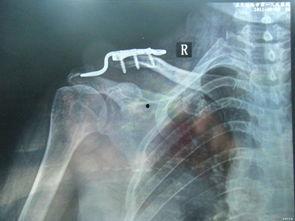

成人肩膀内扣手术,顾名思义,就是针对成年人肩膀内扣问题进行的一种矫正手术。这种手术主要是通过改变肩部肌肉和骨骼的排列,使肩膀恢复到正常的位置。

1. 手术过程视频:这类视频详细展示了手术的整个过程,包括麻醉、手术器械、手术步骤等。通过这些视频,你可以直观地了解手术的全貌。